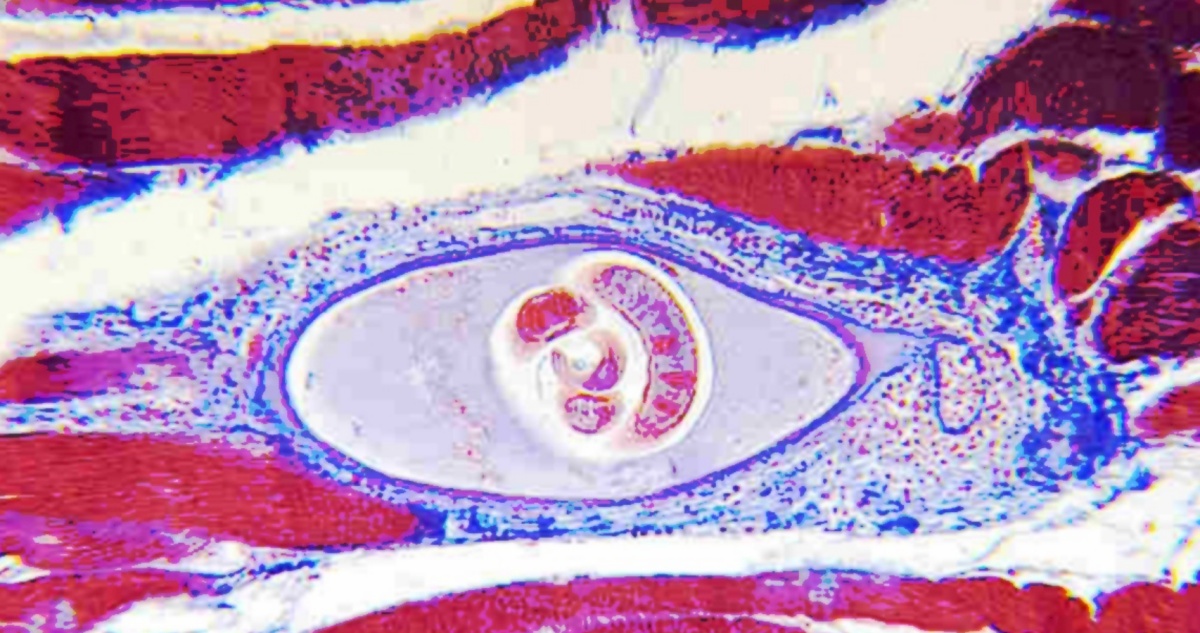

“Le larve infettanti di circa 1 mm di lunghezza, dopo essere state ingerite si liberano dai tessuti dell’ospite nello stomaco, passano all’intestino tenue dove penetrano attivamente nell’epitelio intestinale e si sviluppano fino allo stadio di adulto. Una volta raggiunta la maturità sessuale (al 4° giorno dopo l’infezione) e dopo la successiva fecondazione, la femmina produce larve “newborn” (neonate) che migrano attraverso il sistema linfatico prima e sanguineo dopo, alle cellule dei muscoli striati, dove penetrano attivamente e inducono la cellula a modificarsi in cellula nutrice, differente sia nella struttura che nelle funzioni. Le larve all’interno delle cellule nutrici possono sopravvivere per anni sia nell’uomo che negli animali, restando in attesa di essere ingerite da un nuovo ospite”, viene chiarito dagli esperti.